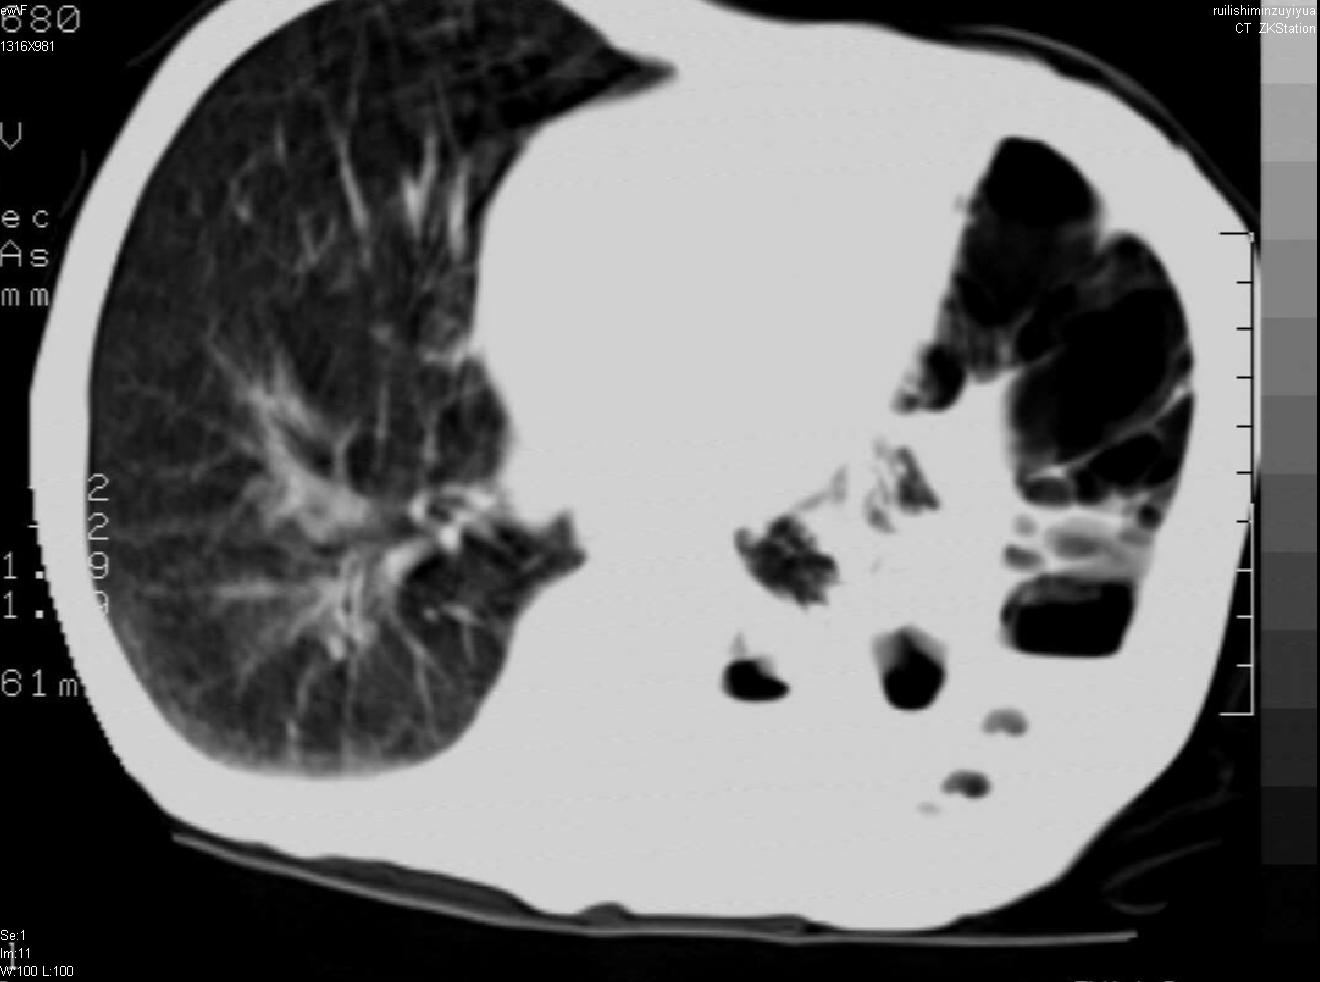

以下是引用天南地北在2007-6-11 23:32:00的发言:[br]1:左侧肺毁损(结核性)伴感染(多发空洞伴液平面)。[br]2:右肺继发型肺结核。

以下是引用avril在2007-6-12 1:17:00的发言:[br]1、左肺毁损。[br]2、左肺多发肺大泡伴自发性气液胸形成。[br]3、右肺继发型结核。